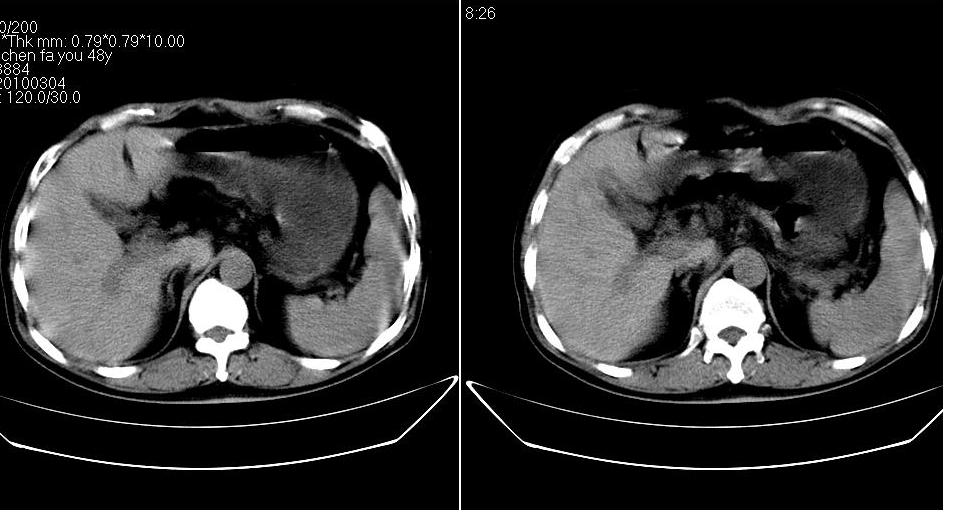

男 48岁,09年8月份在上级医院确诊胰头癌,准备在我院化疗。

胰头体积增大内见低密度影考虑为占位,肿瘤性病变可能性大。

胰头体积增大,外形不规则,密度欠均,支持胰头癌可能性大。